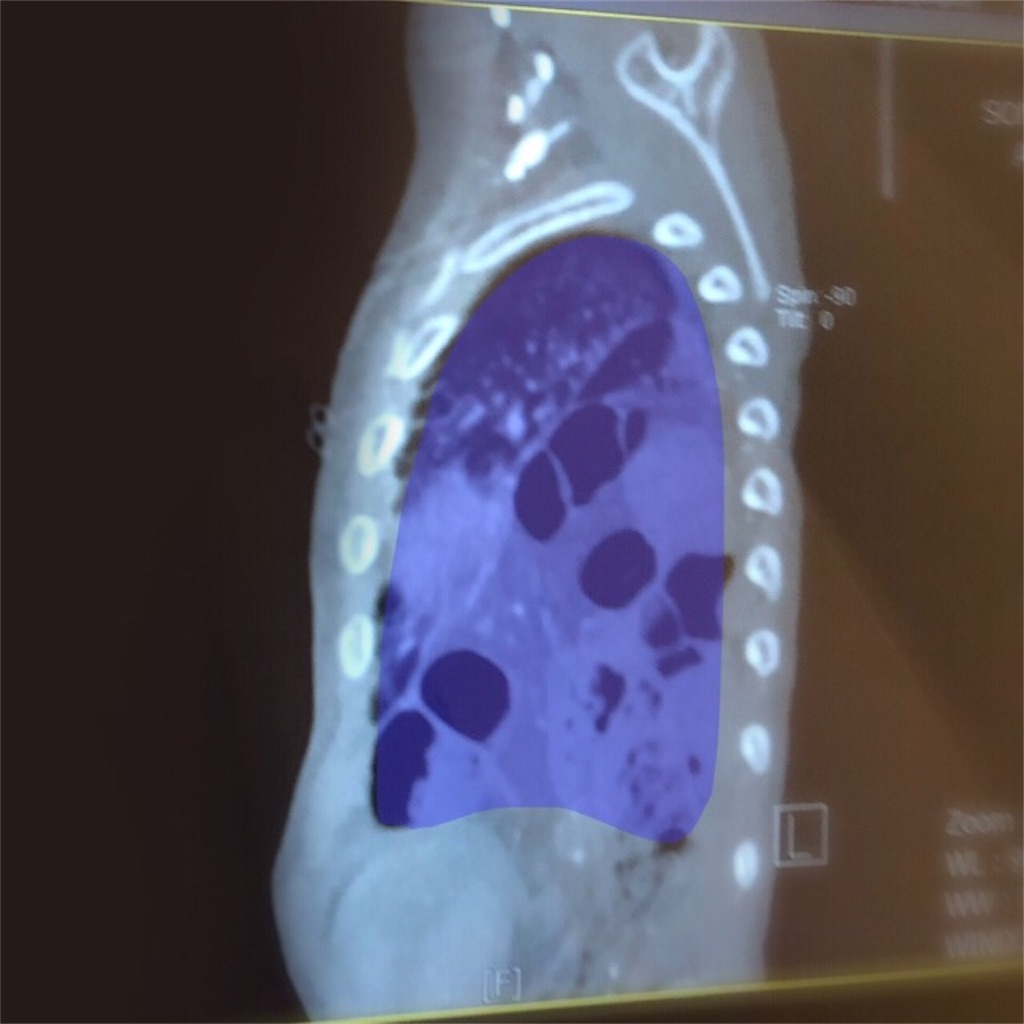

やはり、横隔膜に相当大きな穴があることがわかった。

本来、肺はこの青い部分のように胸骨いっぱいに広がっている。

かなりの体積を占めているのが分かると思う。

半年前のCTでは分からなかったことだ。

衝撃画像……!